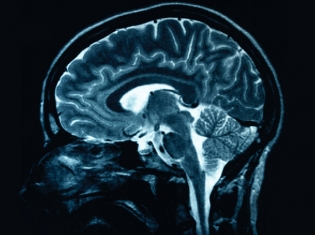

Gene-Jack Wang, a physician at Brookhaven Lab and Mount Sinai School of Medicine, and colleagues examined 10 obese individuals diagnosed with binge eating disorder and eight obese individuals who were not binge eaters. Using positron emission tomography (PET), the researchers scanned subjects' brains in order to study their reactions to the smell and taste of their favorite foods.